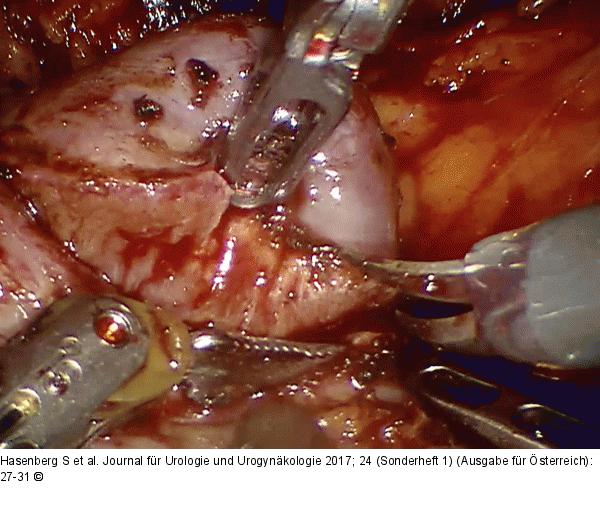

Abbildung 1: Nierenteilresektion

Roboterassistierte Nierenteilresektion, Aufnahme während der Tumorexzision |